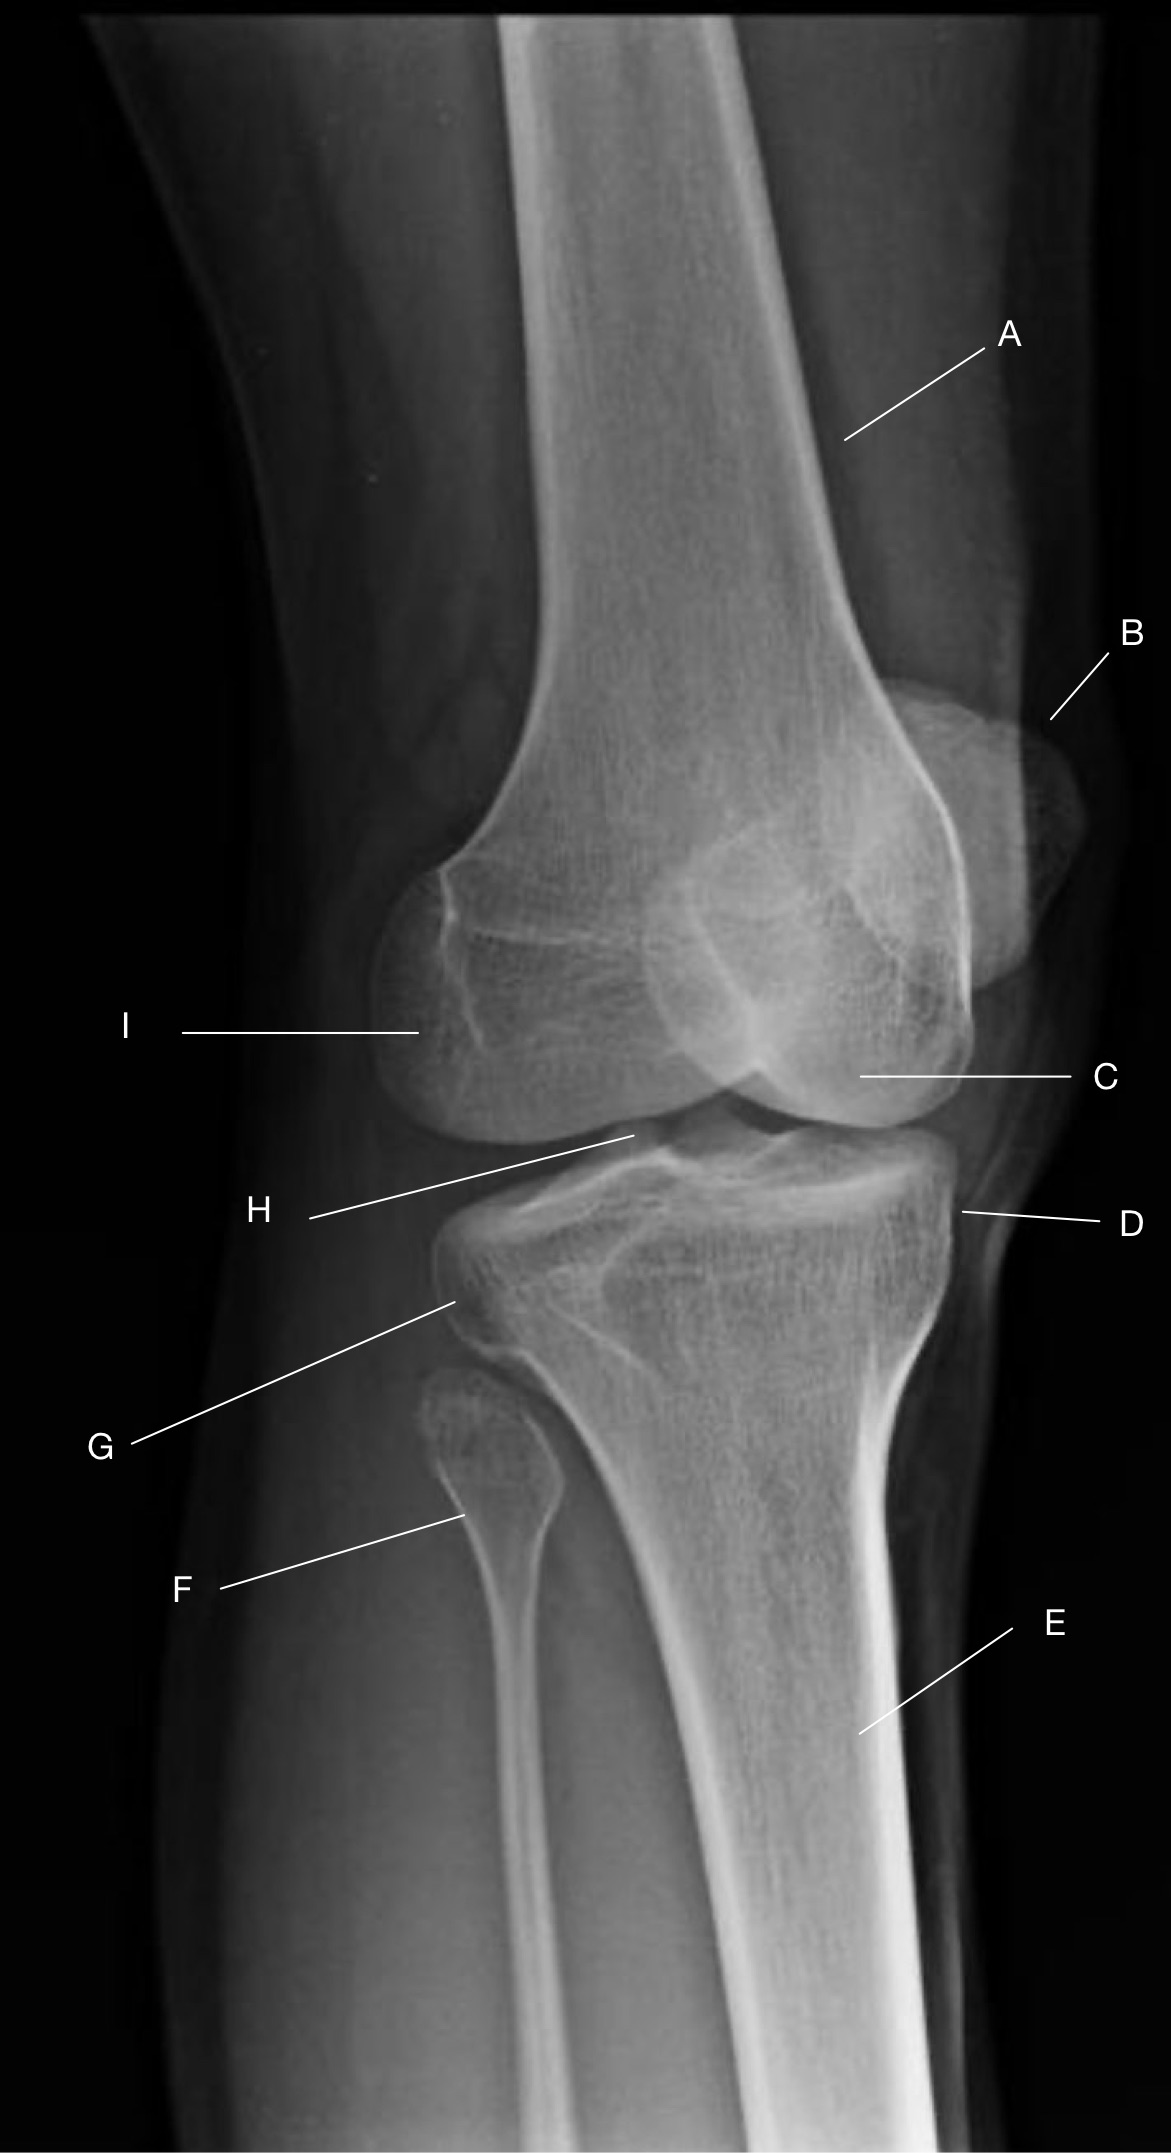

Name the projection.

Should it be repeated, if so why?

AP Knee

No

Label the image

A) Femur

B) Patella

C) Lateral femoral epicondyle

D) Intercondylar fossa

E) Intercondylar eminence

F) Femorotibial joint

G) Fibula

H) Tibia

I) Tibial condylar margin

J) Medial femoral epicondyle